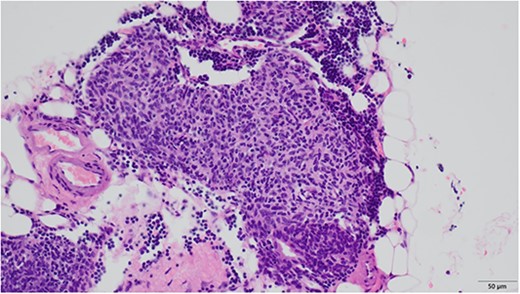

An 81-year-old woman was referred to our hospital because of right lung cancer. She underwent right upper lobectomy by video-assisted thoracic surgery. Pathological examination revealed stage 1A adenocarcinoma. Four months postoperatively, chest computed tomography showed a small nodule with a diameter of 6 mm at the anterior mediastinum (Fig. 1A). After 2 years, the nodule had increased to 13 mm (Fig. 1B). Chest magnetic resonance imaging showed a mediastinal tumor with low-signal intensity on T1-weighted images and high-signal intensity on T2-weighted images, and it was diagnosed as a cystic tumor. For diagnosis and treatment, we resected the tumor and surrounding thymic tissue by a left robotic thoracic approach, considering the adhesion in the right thoracic cavity after right pulmonary resection. The operating time was 43 min, and the blood loss volume was 5 ml. The patient had a favorable postoperative course and was discharged 3 days after surgery. Pathological examination revealed a thymic cyst and microscopic thymoma with a diameter of 400 μm very close to the thymic cyst (Fig. 2).

Microscopic findings revealed nodular hyperplasia of the thymic epithelium with a diameter of 400 μm.